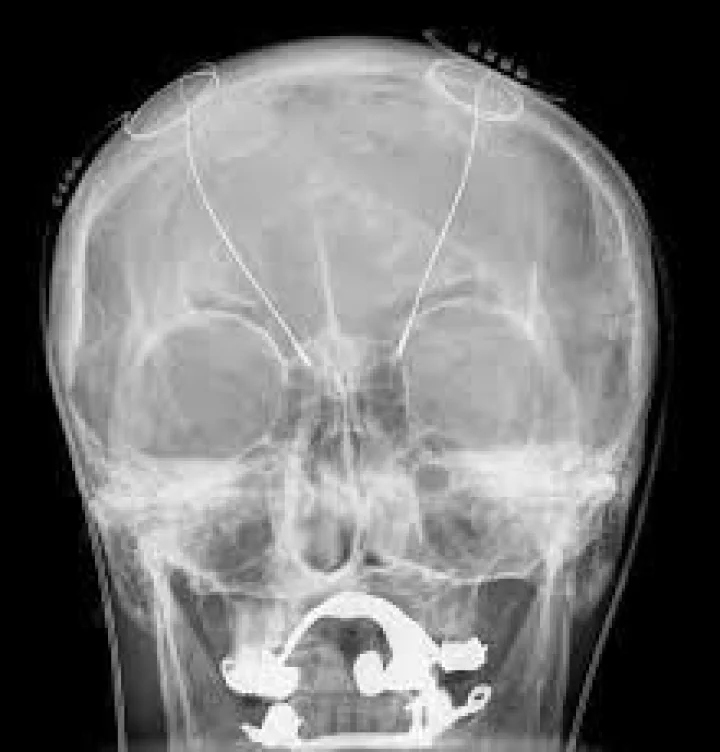

मुंबईतील जसलोक रूग्णालयातील न्यूरोसर्जन डॉ. परेश दोशी व त्यांच्या टिमने ऑटिझम रुग्णांवरील डीप ब्रेन स्टिम्युलेशन हि शस्त्रक्रिया यशस्वीरित्या पार पाडली. आशियात दुसऱ्यांदा अशा प्रकारची शस्त्रक्रिया करण्यात आल्याचं रूग्णालयातर्फे सांगण्यात आलं आहे.

ऑटिझम व अपस्माराची रूग्ण असलेल्या 42 वर्षीय पॅमेला या महिलेवर ही शस्त्रक्रिया करण्यात आली. या शस्त्रक्रियेत वापर करण्यात आलेले तंत्रज्ञान आधीच्या डीबीएस उपकरणांपेक्षा अधिक प्रभावी आहे. या शस्त्रक्रियेत वापरण्यात येणाऱ्या बॅटरीचे आयुष्य अत्यल्प होते. मात्र यावेळी बोस्टन सायन्टिफिकच्या नव्या व्हेरसाईस सिस्टिममुळे बॅटरीचे आयुष्य जवळपास 25 वर्षानी वाढले आहे. या शस्त्रक्रियेदरम्यान बऱ्याचदा डॉक्टरांना अनेक समस्यांना सामरे जावे लागते. या आजारतील रूग्णांचा परिणाम हा त्यांच्या कुटुंबियांवरदेखील होत असतो. डीबीएस या शस्त्रक्रियेमार्फत त्यांच्यातील मेंदूचे संतुलन साधणे सोपे होत असल्याचे डॉक्टर सांगतात. पॅमेला यांना वयाच्या तिसऱ्या वर्षापासून ऑटिझम हा आजार आहे. या आजारात व्यक्तीला वागणूक, इतरांशी बोलणे, हावभाव किंवा सार्वजनिक ठिकाणी लोकांशी संवाद साधताना अडचणी निर्माण होतात. जसलोक रूग्णालयात येण्यापूर्वी पॅमेला यांची अवस्था फारच ढासाळली होती. त्यांचा स्वत:च्या परिवारासोबत आक्रमकपणा वाढला. अमेरिकेतल्या बऱ्याच वेगवेगळ्या डॉक्टरांचे शस्त्रक्रियेसाठीचे सल्ले घेतल्यानंतर जर्मनीतील एका डॉक्टरने पॅमेला यांच्यावर शस्त्रक्रिया करण्यास होकार दिला मात्र काही कारणांमुळे त्यांनी काही दिवसांनी नकार दिला.

बऱ्याचदा संवाद केल्यानंतर जसलोक रूग्णालयातील मानसोपचार तज्ज्ञ असलेल्या डॉ. अमित देसाई यांनी पॅमेला यांच्या आजारावर अभ्यास केला. त्यानंतर पॅमेला यांच्यावर शस्त्रक्रिया होऊ शकते असा निकष काढण्यात आला. यानुसार पॅमेलावर 7 मार्चला शस्त्रक्रिया करण्यात आली. शस्त्रक्रियेनंतर त्यांच्या प्रकृतीत कमालीची सुधारणा झाली. त्यांची वागणूक, लोकांशी बोलण्याची पद्धत अशा सर्व गोष्टींमध्ये कमालीचा फरक पडला.

मानसिक उपचार बऱ्याचदा केल्यानंतर पॅमेलावर केलेली सर्जरी ही अत्यंत किचकट होती. ऑटिझम वर उपचार केल्यानंतर अपस्माराची रिस्कही लक्षात घेत ही शस्त्रक्रिया करण्यात आली आहे, असे न्युरोसर्जन डॉ. परेश दोशी यांनी यावेळी सागंतिले.